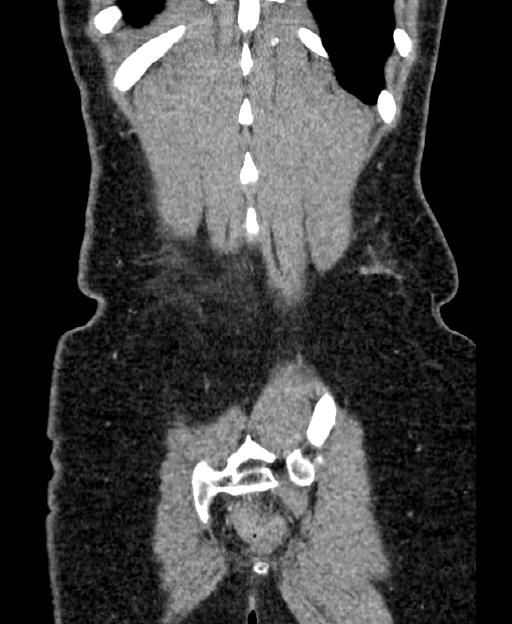

8 months of chest pain, breathing difficulties, new onset asthma and allergies. Low grade fever. One month of severe itch and rashes. Numbness, eye problem, general weakness and abdominal, back and pelvic pain. Weight loss. Fluctuating blood pressure and occasionally increased pulse pressure. Memory problem and fatigue. Feeling of neck tightness.

PIP breast implant in 2002.